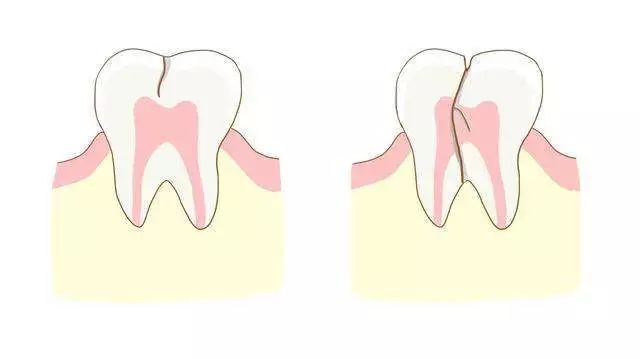

儿童换牙双层牙图片,

重双层牙图片,

- 【口腔微学院】太吓人,我家宝宝长出双层牙,我该肿么

- 没听说过双层牙孩子5岁还不注意就晚啦!

- 操作三:及时处理双层牙

- 孩子怎么长了双排牙还不是家长喂出来的

- 细致呵护,让孩子远离双层牙

- 儿童龋齿/双排牙,家长总是忽视